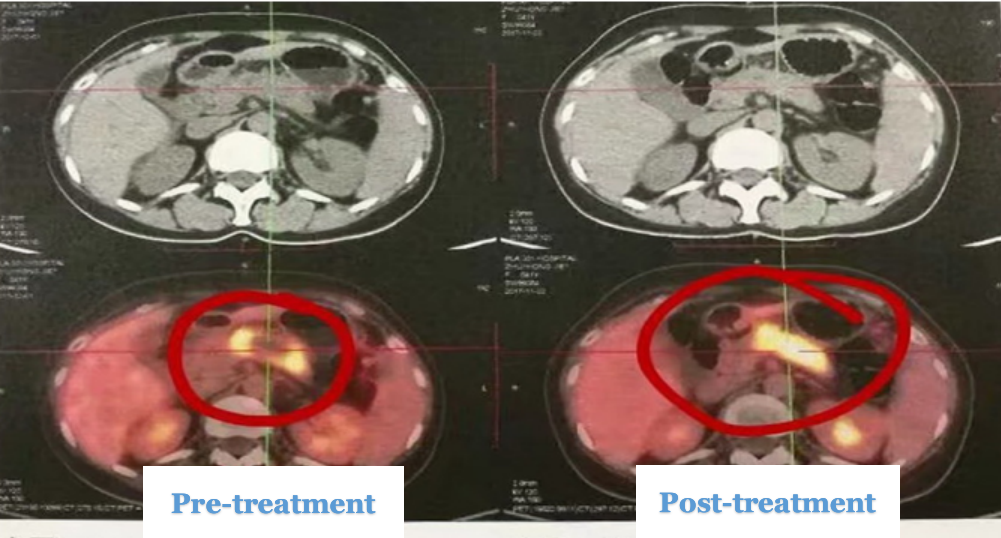

Pancreatic Cancer Treatment Case 5:

Patient: Female, 41 years old, pancreatic cancer

After 9 days of HIFU treatment, a follow-up PET-CT scan showed extensive necrosis at the center of the tumor.